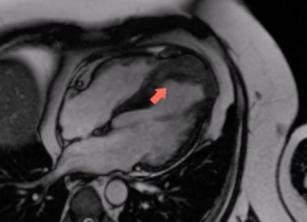

How to assess a left ventricular thrombus with the help of cardiac MRI (CMR) 13th Sep 2017 - Andrew R. Houghton, MD Assessing a left ventricular thrombus with echo can be a tricky thing. CMR can come in really handy in these ...